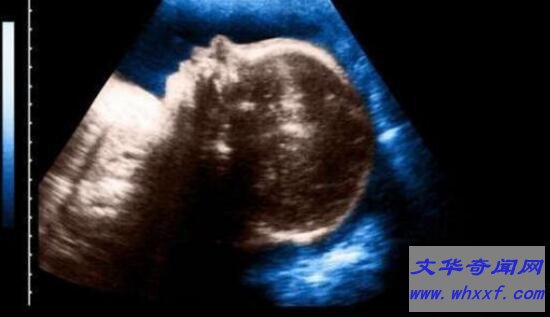

虽然这种畸形的发生不算罕见,但是通过孕期的超声检查,有86%的病例是能够被查处。曾有报道,南京的唐女士因长期受新车内超标甲醛的影响,在孕期第三个月进行超声检查时,竟然查出胎儿存在畸形问题,不得不引产,结果真的引产出一个已死亡的一只眼的婴儿。